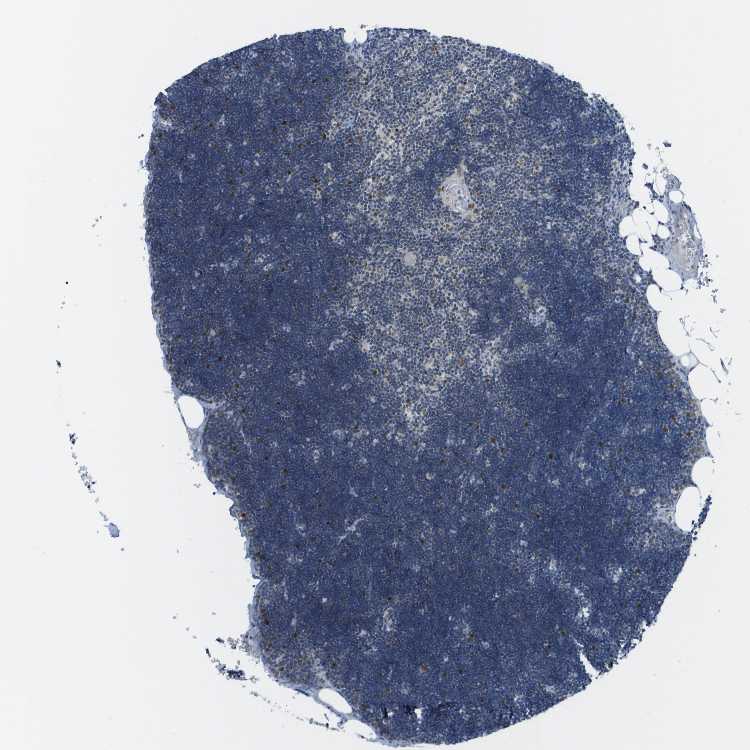

TISSUE PRIMARY DATA LYMPH NODE Show tissue menu

LYMPH NODE - Antibody stainingi

Antibody staining in the annotated cell types in the current human tissue is reported as not detected, low, medium, or high, based on conventional immunohistochemistry profiling in selected tissues. This score is based on the combination of the staining intensity and fraction of stained cells.

Each image is clickable and will lead to virtual microscopy that enables deeper exploration of all samples and also displays staining intensity scores, fraction scores and subcellular localization as well as patient and tissue information for each sample.

Antibody HPA016511

Germinal center cells Low

Non-germinal center cells Low